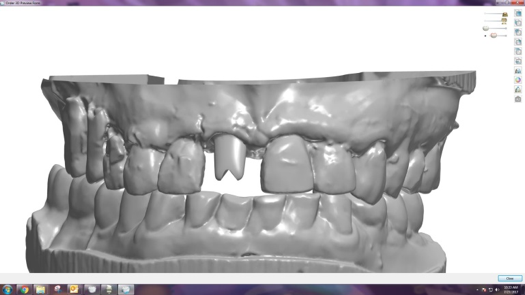

Fig 33. CBCT imaging merged with scanned impressions.

Figure 33